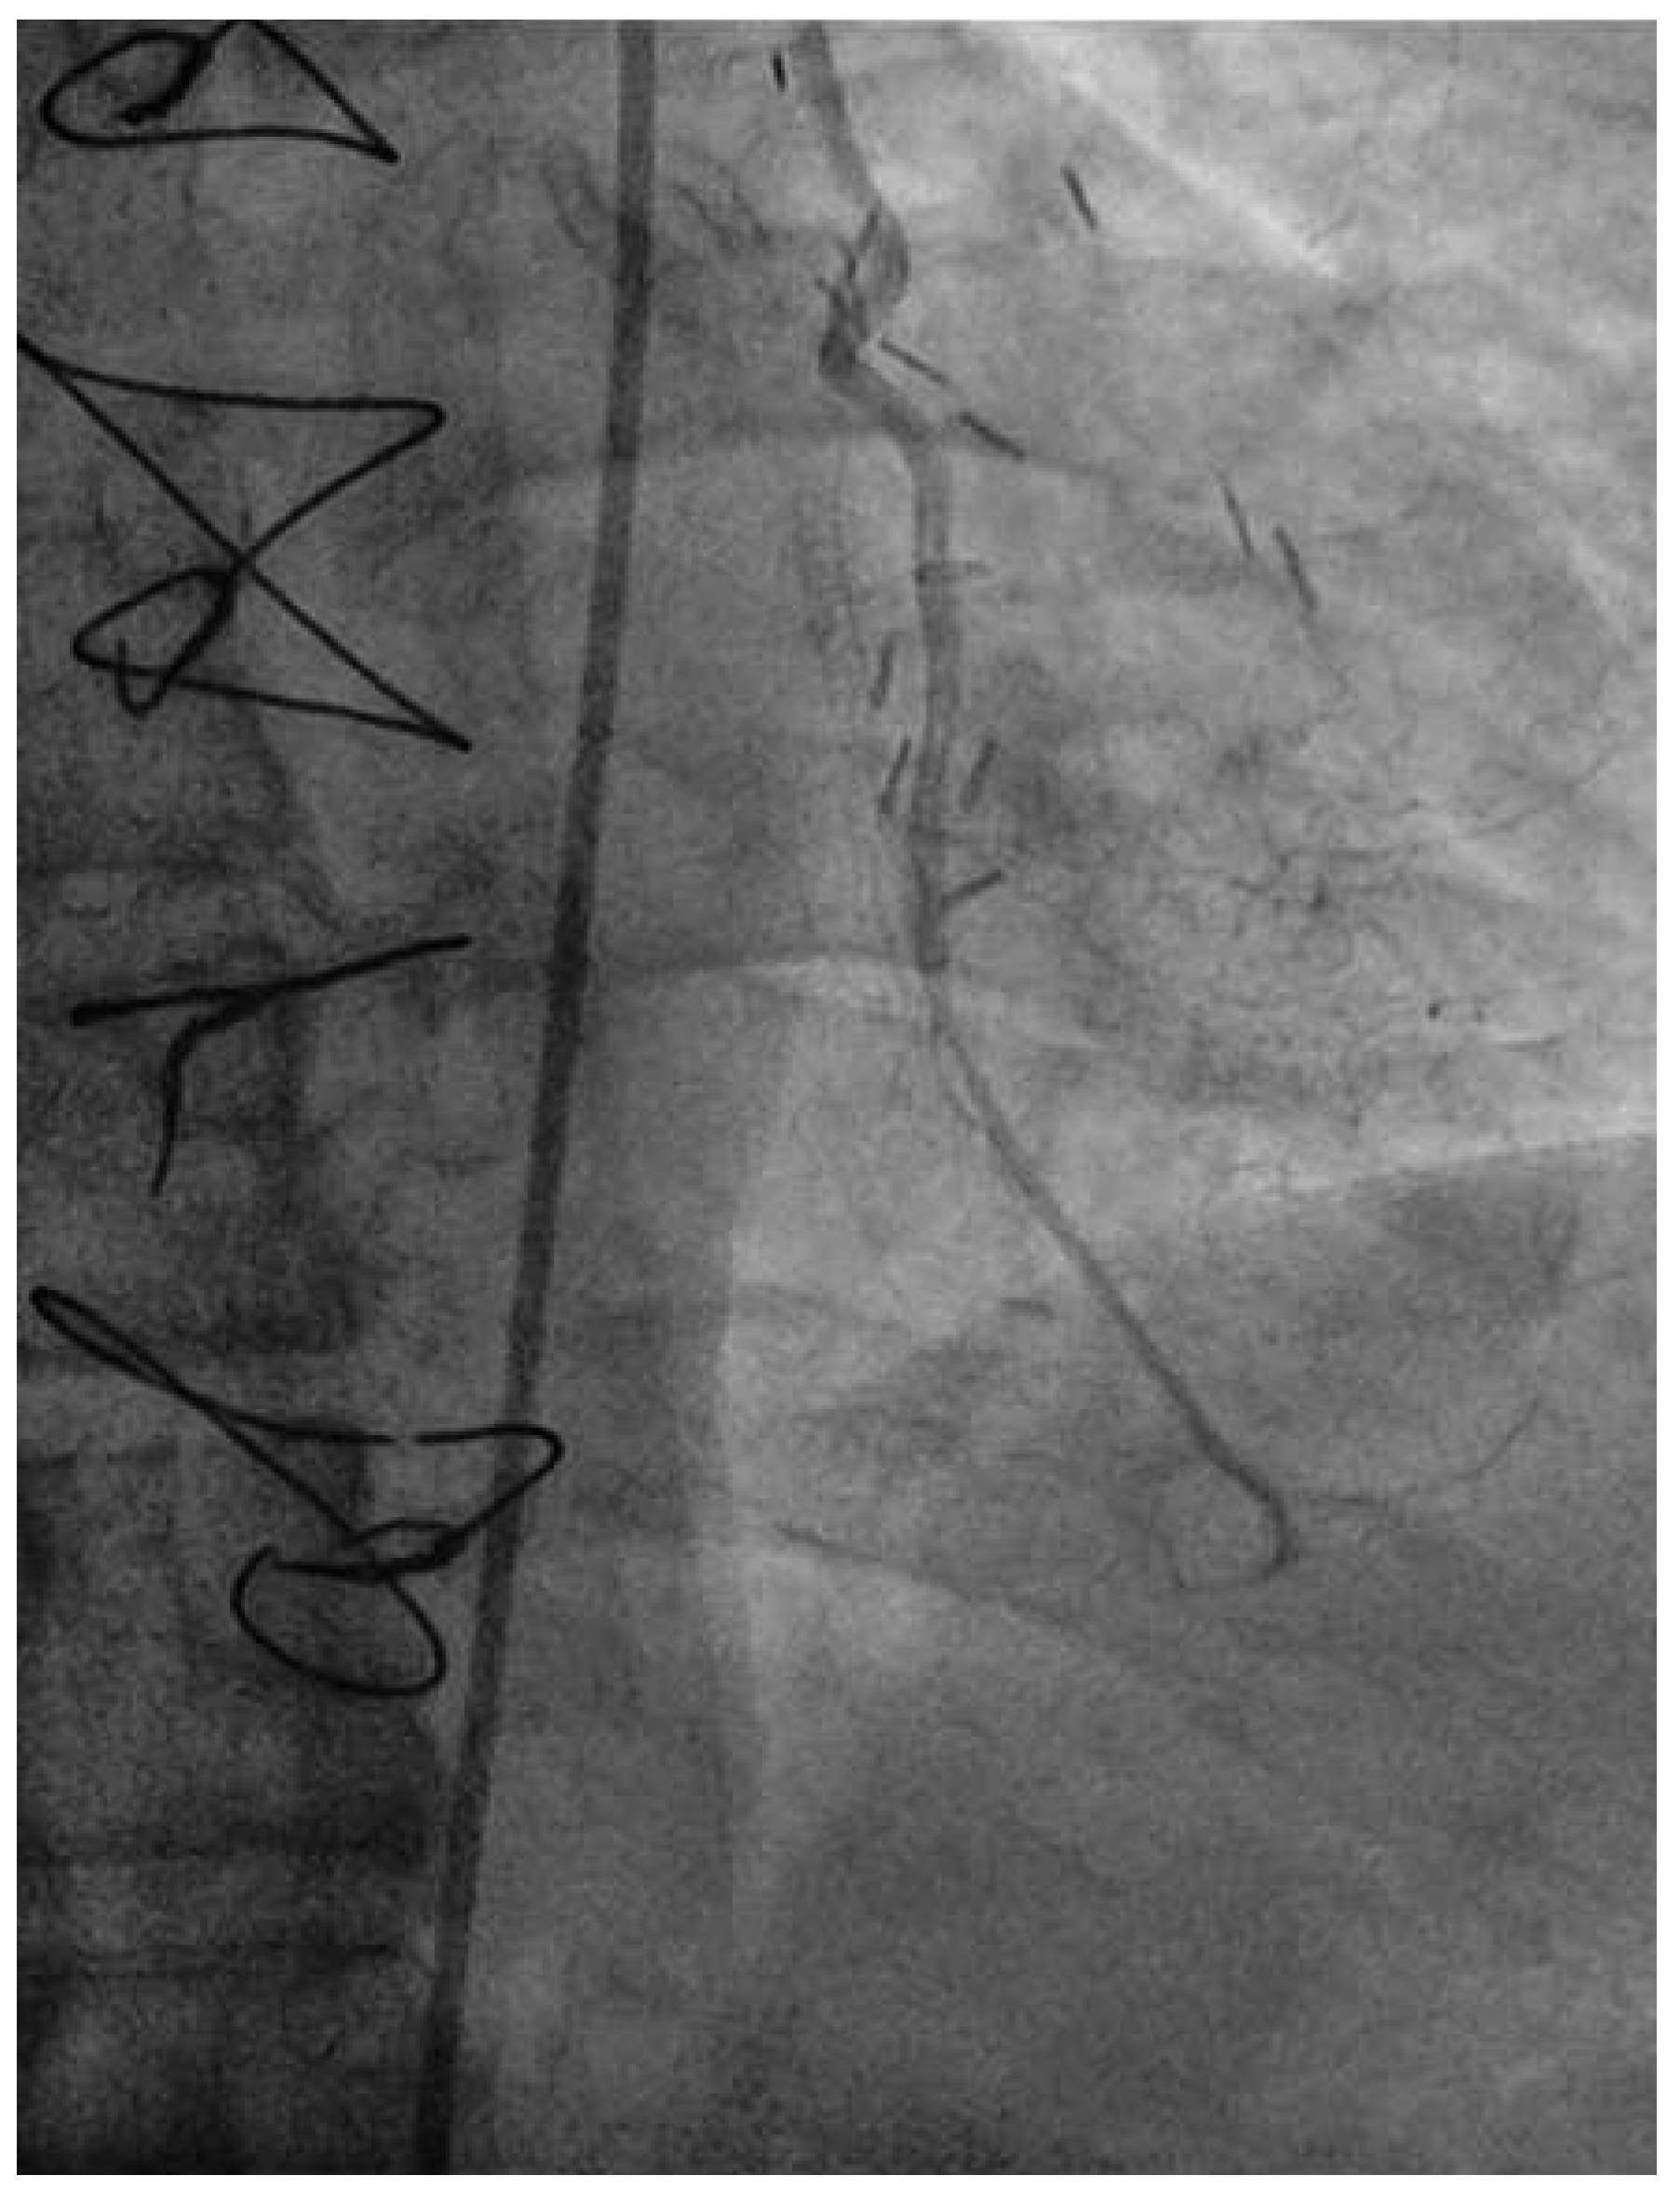

Following RA, both LAD and diagonal were wired with ease using separate Runthrough (Terumo, Japan) wires. Predilatation of both bifurcation limbs was undertaken using 1.5 × 15 mm Trek (Abbott) and 2.0 × 10 mm Sapphire (Orbus-Neich, Hong Kong, China) semicompliant balloons, which both expanded well at nominal pressure. Intending to perform an elective T-stent strategy, a 2.25 × 28 mm Promus Premier DES was deployed at 18 Atm in the diagonal branch, landing proximally at the ostium of this vessel (Figure 3). After removal of the diagonal wire, a 3 × 38 Promus Premier stent (Boston Scientific) was sited from the origin of the LMS across the first diagonal and deployed at 18 Atm (Figure 4). The diagonal branch was then rewired with the runthrough wire. A kissing inflation was performed at 12 Atm using a 3.5 × 12 Quantum (Boston Scientific) and 2.5 × 12 Sapphire noncompliant (NC) balloons in LAD and diagonal, respectively (Figure 5A). The proximal LAD and LMS were then optimised using the 3.5 Quantum NC (LAD) and a Hiryu (Terumo) 4 × 10 NC (LMS) balloons at 22 and 18 Atm, respectively (Figure 5B). The final angiographic result was excellent (Figure 6). Intravascular ultrasound of the LMS was not undertaken as angiographically the LMS stent already appeared completely expanded and oversized. We opted not to intervene in the ostial left Cx in order to best preserve the geometry of the LMS stent.

Figure 6. LAO 30°, cranial 30° views of final angiographic result.